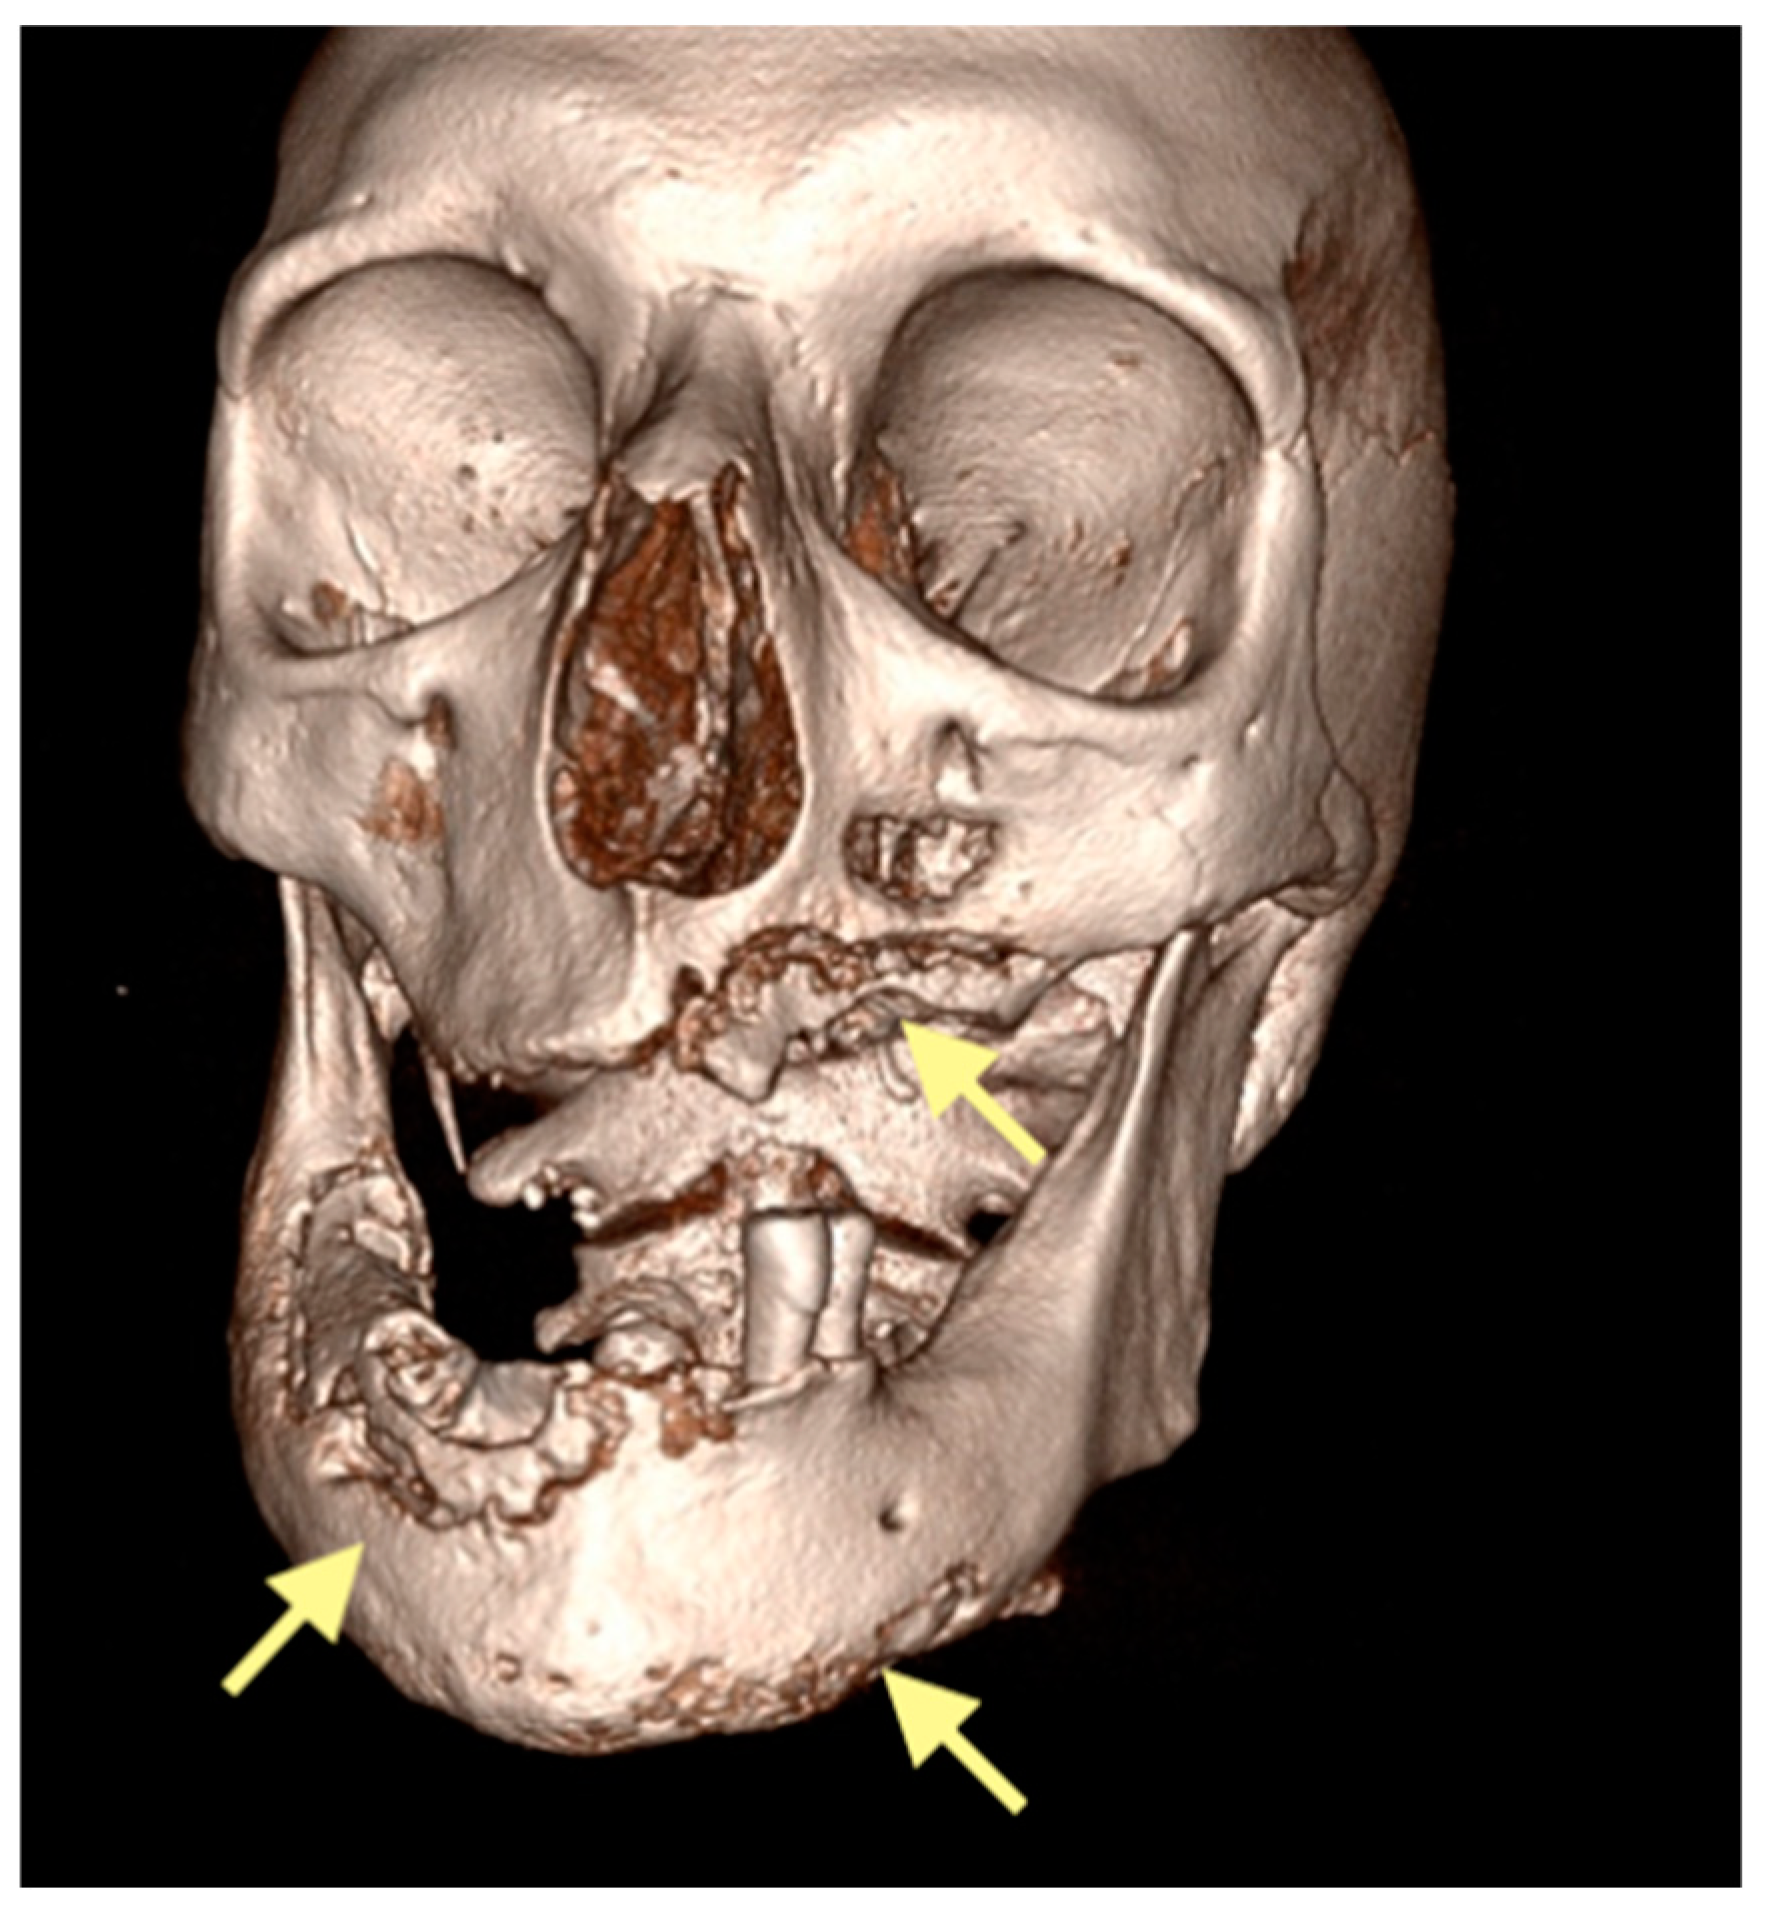

The third patient was a 75-year-old female with osteonecrosis of the mandible and maxilla in the fourth and in the second quadrant (see Figure 7, Figure 8 and Figure 9). The patient had third-stage jaw osteonecrosis. In 2023, the patient was diagnosed with osteonecrosis of the upper and lower jaw caused by antiresorptive therapy (until August 2021, the patient regularly used Zolendronic acid; then, this drug was replaced by the RANKL inhibitor Denosumab). The treatment was periodically complicated by submandibular and submental abscesses. In addition, due to the progression of the underlying disease, constant courses in chemotherapy were administered. The patient underwent three operations, which included sequestrectomy of the jaw with simultaneous use of A-PRF, antrotomy with revision of the maxillary sinus, closure of the oroantral communication, and opening and revision of abscesses of the soft tissues (see Figure 10 and Figure 11)

Figure 10.

CT of the head and facial bones (19 March 2025) before the last operation (sequestrectomy of the lower and upper jaws; antrotomy performed).